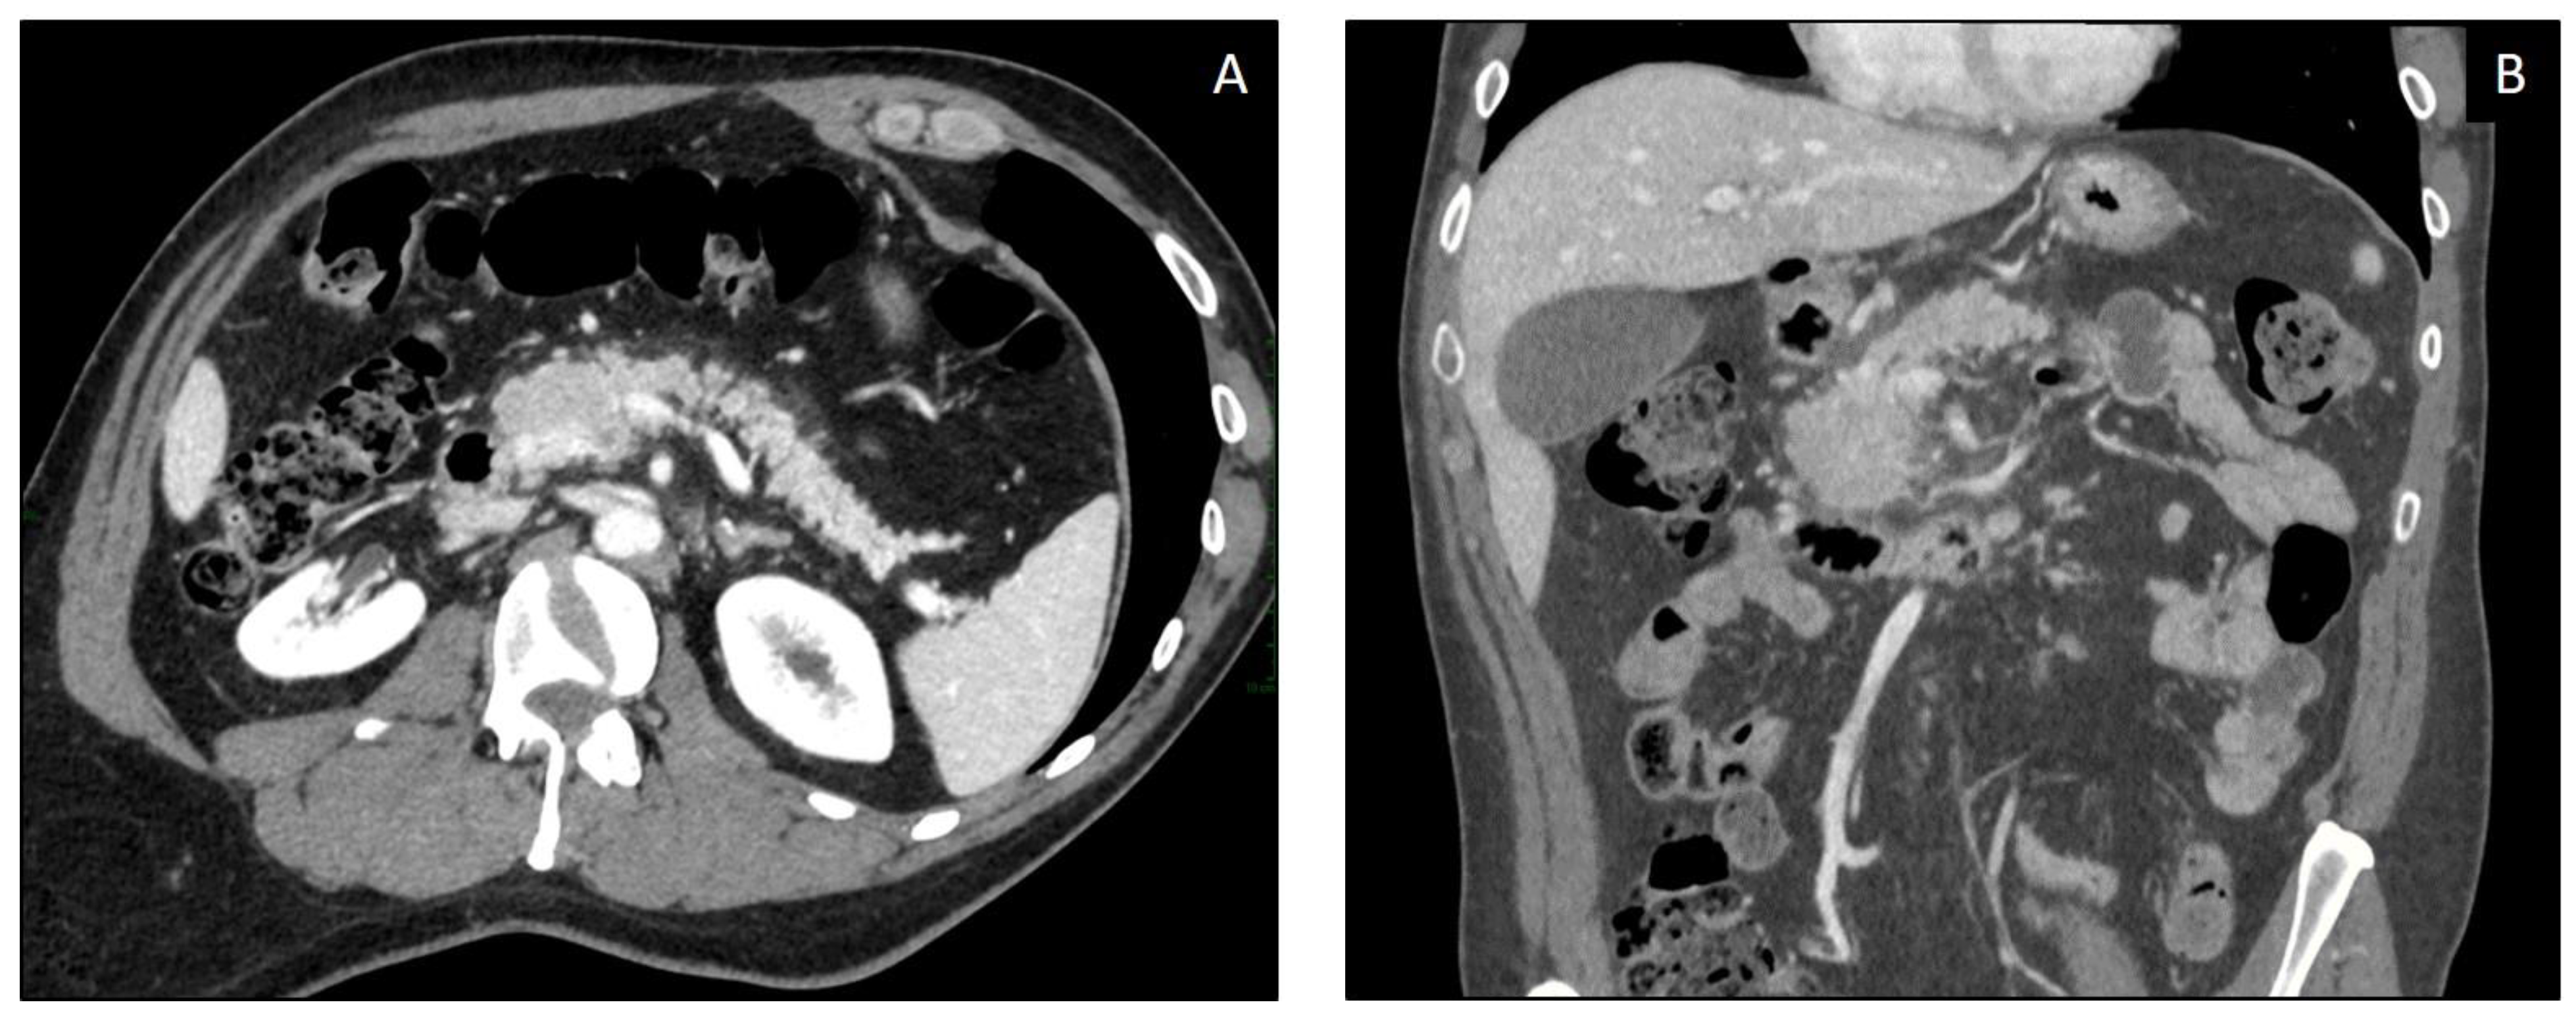

4.3. Diagnosis and Imaging

| Imaging Modality | ICIPI Imaging Findings (IEP > NP) |

| CT | IEP

|

| MRI | IEP With edematous pancreatic regions:

with necrotic areas involving pancreatic gland and/or peripancreatic spaces:

| PET-CT (18F-FDG) |

4.4. Differential Diagnosis